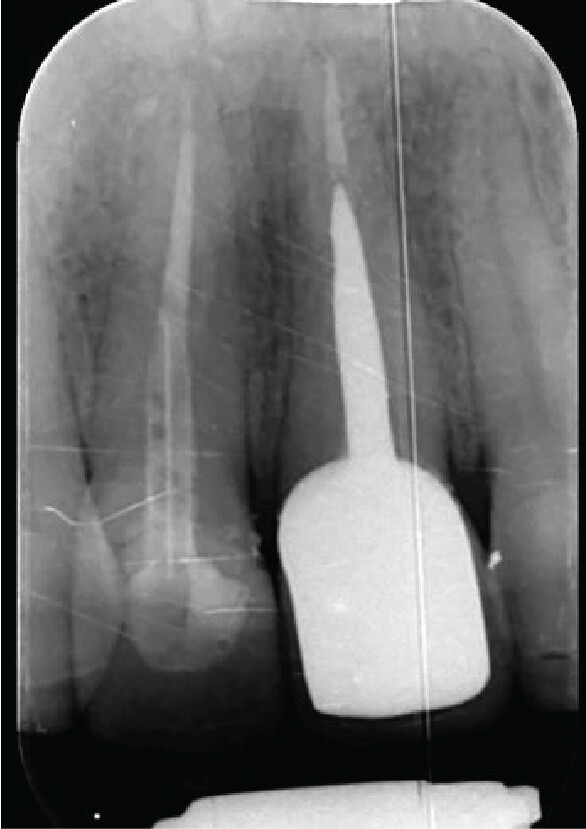

Question 1: What materials cannot be seen in the print of the X ray?

Question2: Which surface shows overhang?

Question 3: Which option is not evident on the print of the X ray?

Question 4: Which options cannot be seen in the print of the X ray?

Question 5: What options cannot be selected for tooth # 4.6?

Question 6: What options cannot be seen in the print of the X ray?

Question 7: What option cannot be identified on the print of the X ray?

Question 8: What condition can be seen in the X ray?

Question 9: Which option cannot be seen in the lower jaw?

Question 10: Which option can be selected for the following X ray?

Question 11: Which materials cannot be seen in the print of the X ray?

Question 12: What option cannot be selected for the following X ray?

Question 13: What option cannot be selected for the following X ray?

Question 14: Which surface shows overhang restoration?

Question 15: Which surface shows overhang in the restoration?

Question 16: Which surface shows overhang?

Question 17: Which surface shows overhang?

Question 18: Which surface shows overhang?

Question 19: Which option can be chosen for the tooth # 3.6?

Question 20: which tooth shows defective resotration?

Question 21: What option is can be selected for distal tooth # 4.6?

Question 22: Which surface shows defective restoration?

Question 23: Which surface shows overhang?

Question 24: Which surface shows defective restoration?

Question 25: Which surface shows open margin?